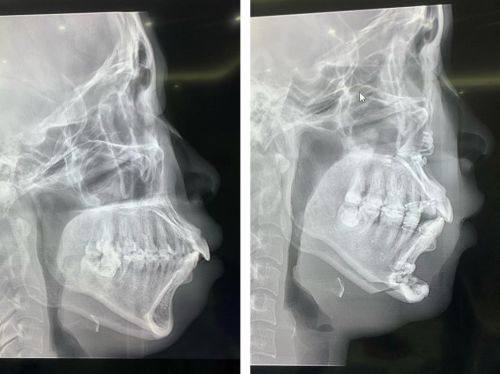

牙齿畸形矫正:杨四维医生专注各类牙齿畸形矫正项目,能够根据患者的口腔基础条件定制个性化矫正方案,兼顾口腔功能修复与面部美观提升,帮助患者改善牙齿排列问题,优化口腔健康状态与整体魅力。

拥有海外进修学习经历,将国内外精良的口腔正畸技术融入国内临床诊疗,诊疗方案科学合理,注重患者的诊疗体验,能够耐心与患者沟通,让患者清晰了解矫正流程与预期成效。